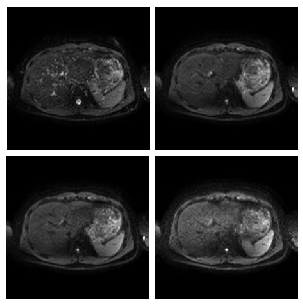

ABSTRACT: Registration of diffusion weighted datasets remains a challenging task in the process of quantifying diffusion indexes. Respiratory and cardiac motion, as well as echo-planar characteristic geometric distortions, may greatly limit accuracy on parameter estimation, specially for the liver. This work proposes a methodology for the non-rigid registration of multiparametric abdominal diffusion weighted imaging by using different well-known metrics under the groupwise paradigm. A three-stage validation of the methodology is carried out on a computational diffusion phantom, a watery solution phantom and a set of voluntary patients. Diffusion estimation accuracy has been directly calculated on the computational phantom and indirectly by means of a residual analysis on the real data. On the other hand, effectiveness in distortion correction has been measured on the phantom. Results have shown statistical significant improvements compared to pairwise registration being able to cope with elastic deformations.